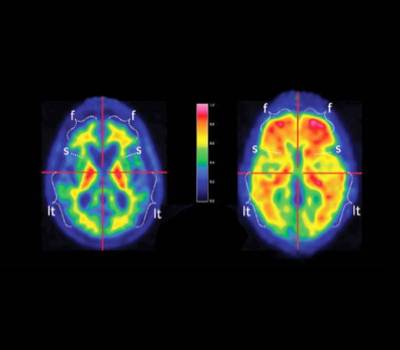

Los primeros indicios del alzhéimer pueden llegar a confundirse con los propios efectos del envejecimiento, lo que dificulta el diagnóstico hasta que se identifican síntomas demasiado evidentes del deterioro. Sin embargo, se han observado ciertas alteraciones cerebrales que pueden originarse entre 15 y 20 años antes de los primeros síntomas. En este sentido, nuestro doctor nos explica que "la detección de ciertas proteínas, como la beta amiloide o la Tau en el líquido cefalorraquídeo, o a través de estudios de PET cerebral, son los biomarcadores más destacados para un diagnóstico temprano y certero de la enfermedad".